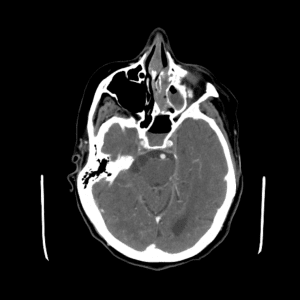

PICA infarct

Case #4